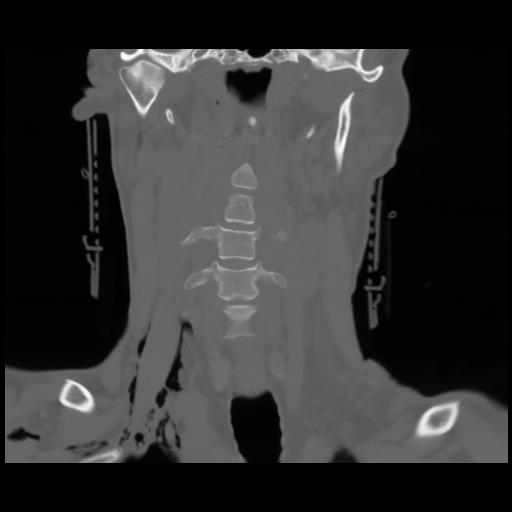

13 P.BLANDAS,,Coronal,2.000,P.BLANDAS,Coronal,